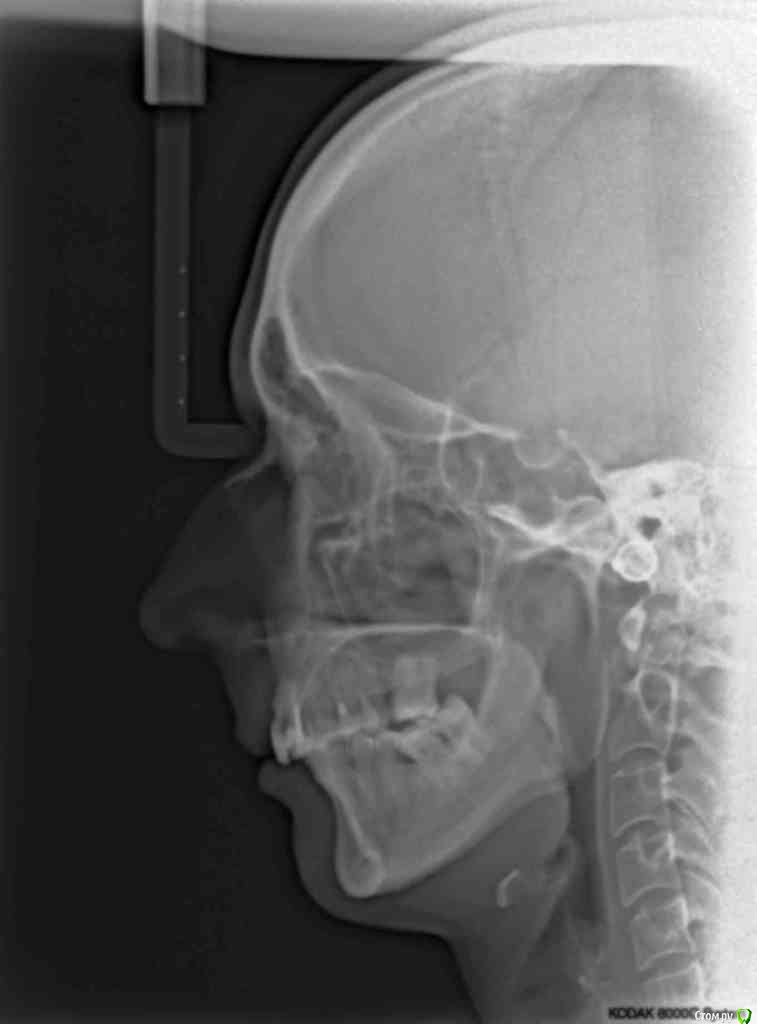

VVQW Опубликовано 6 декабря, 2016 Поделиться Опубликовано 6 декабря, 2016 (изменено) Более 10 лет назад была установлена брекет-система.Лечение было проведено на глаз, анализы и диагностика не проводилась. Спустя время- итог. Сверху перед установкой врач принял решение удалить 6-ки, 8-ки -не выросли. Промежутки между 7-ми и 5-ми - не дотянул и бросил врач. На нижней челюсти системы не было, нижние 6-ки потеряны лет до 14 (в подростковом возрасте). Сейчас процес -усугубляются клиновидки, оголение . Что можно сделать? http://s019.radikal.ru/i641/1612/eb/3498e6cec3f8.jpg http://s018.radikal.ru/i518/1612/73/739600b6d2d1.jpg http://s011.radikal.ru/i318/1612/73/443e1513aaf8.jpg http://s017.radikal.ru/i403/1612/86/73e0dfe4ca62.jpg http://s018.radikal.ru/i518/1612/a2/bd7078537d9e.jpg http://s017.radikal.ru/i417/1612/9d/41b6d1c98666.jpg http://s019.radikal.ru/i642/1612/fe/3222fa19d517.jpg Гипсовых моделей нет, зубы неподвижны. http://s019.radikal.ru/i639/1612/56/1345f17db908.jpg http://s019.radikal.ru/i630/1612/55/145ef7c813b2.jpg http://s017.radikal.ru/i440/1612/c2/74bd4da2643e.jpg http://s008.radikal.ru/i303/1612/b4/e80683ed7d2b.jpg http://s010.radikal.ru/i314/1612/74/6d2f9671b0d5.jpg http://s018.radikal.ru/i502/1612/97/9a15fcf4ddd3.jpg http://s020.radikal.ru/i715/1612/59/9bb4a006621f.jpg Изменено 6 декабря, 2016 пользователем VVQW Ссылка на комментарий